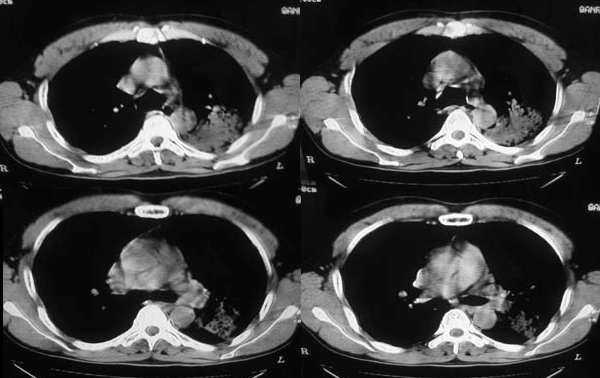

以下是引用ysxyy在2006-3-4 20:19:00的发言:[br]首先考虑炎症,tb暂不考虑;[br]理由:1、病变范围局限在左上肺尖后段,界限较清;[br]2、病史:青壮年34岁,以咳嗽、发热就诊,急性起病;[br]3、

以下是引用lkc8963在2006-3-4 21:27:00的发言:[br][quote]以下是引用ysxyy在2006-3-4 20:19:00的发言:[br]首先考虑炎症,tb暂不考虑;[br]理由:1、病变范围局限在左上肺尖后段,界限较清;[br]2、病史:青壮年34岁,以咳嗽、发热就诊,急性起病;[br]3、